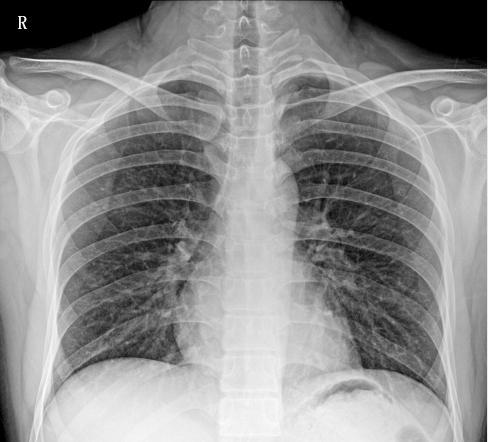

臨床圖像